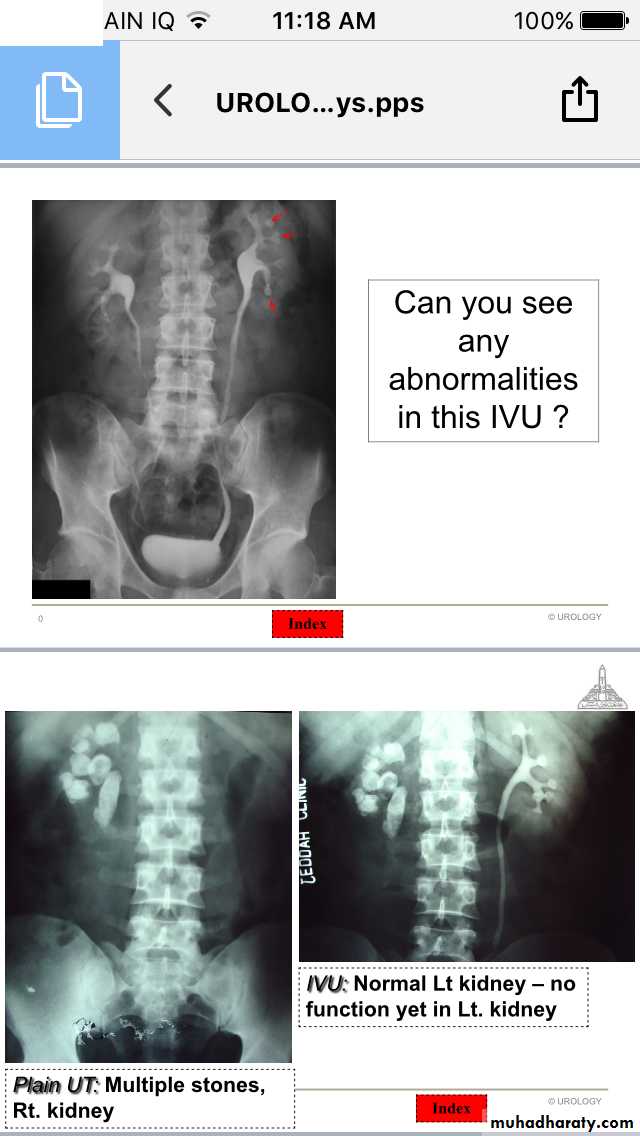

IVU

Renal stones

Urinary Stones